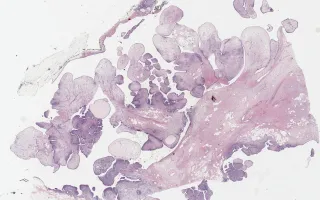

Details

7.4 cm right breast lump.

Phyllodes tumours are fibroepithelial tumours that arise from intralobular stroma of the breast. The lesions have a 'leaf like' configuration, hence the Greek name 'phyllodes.' They mostly occur in the sixth decade, but can occur at any age. Criteria to differentiate between benign, borderline, and malignant include the degree of stromal cellularity and atypia, mitotic count, stromal overgrowth, and the nature of their tumour borders. While benign and borderline phyllodes tumours recur locally and rarely metastasize, malignant phyllodes tumours can develop distant metastases in about 15% of the cases. Excision with wide (at least 1 cm) margins with no lymph node dissection is the treatment of choice for malignant phyllodes tumours, with adjuvant radiation therapy sometimes given to large (over 10 cm) lesions or lesions with incomplete excision.

Findings in this case suggestive of malignancy include: marked hypercellularity, marked nuclear atypia, high mitotic count (up to 21 mitotic figures per 10 HPF), stromal overgrowth, infiltrative borders and heterologous elements in the form of adipocytes.